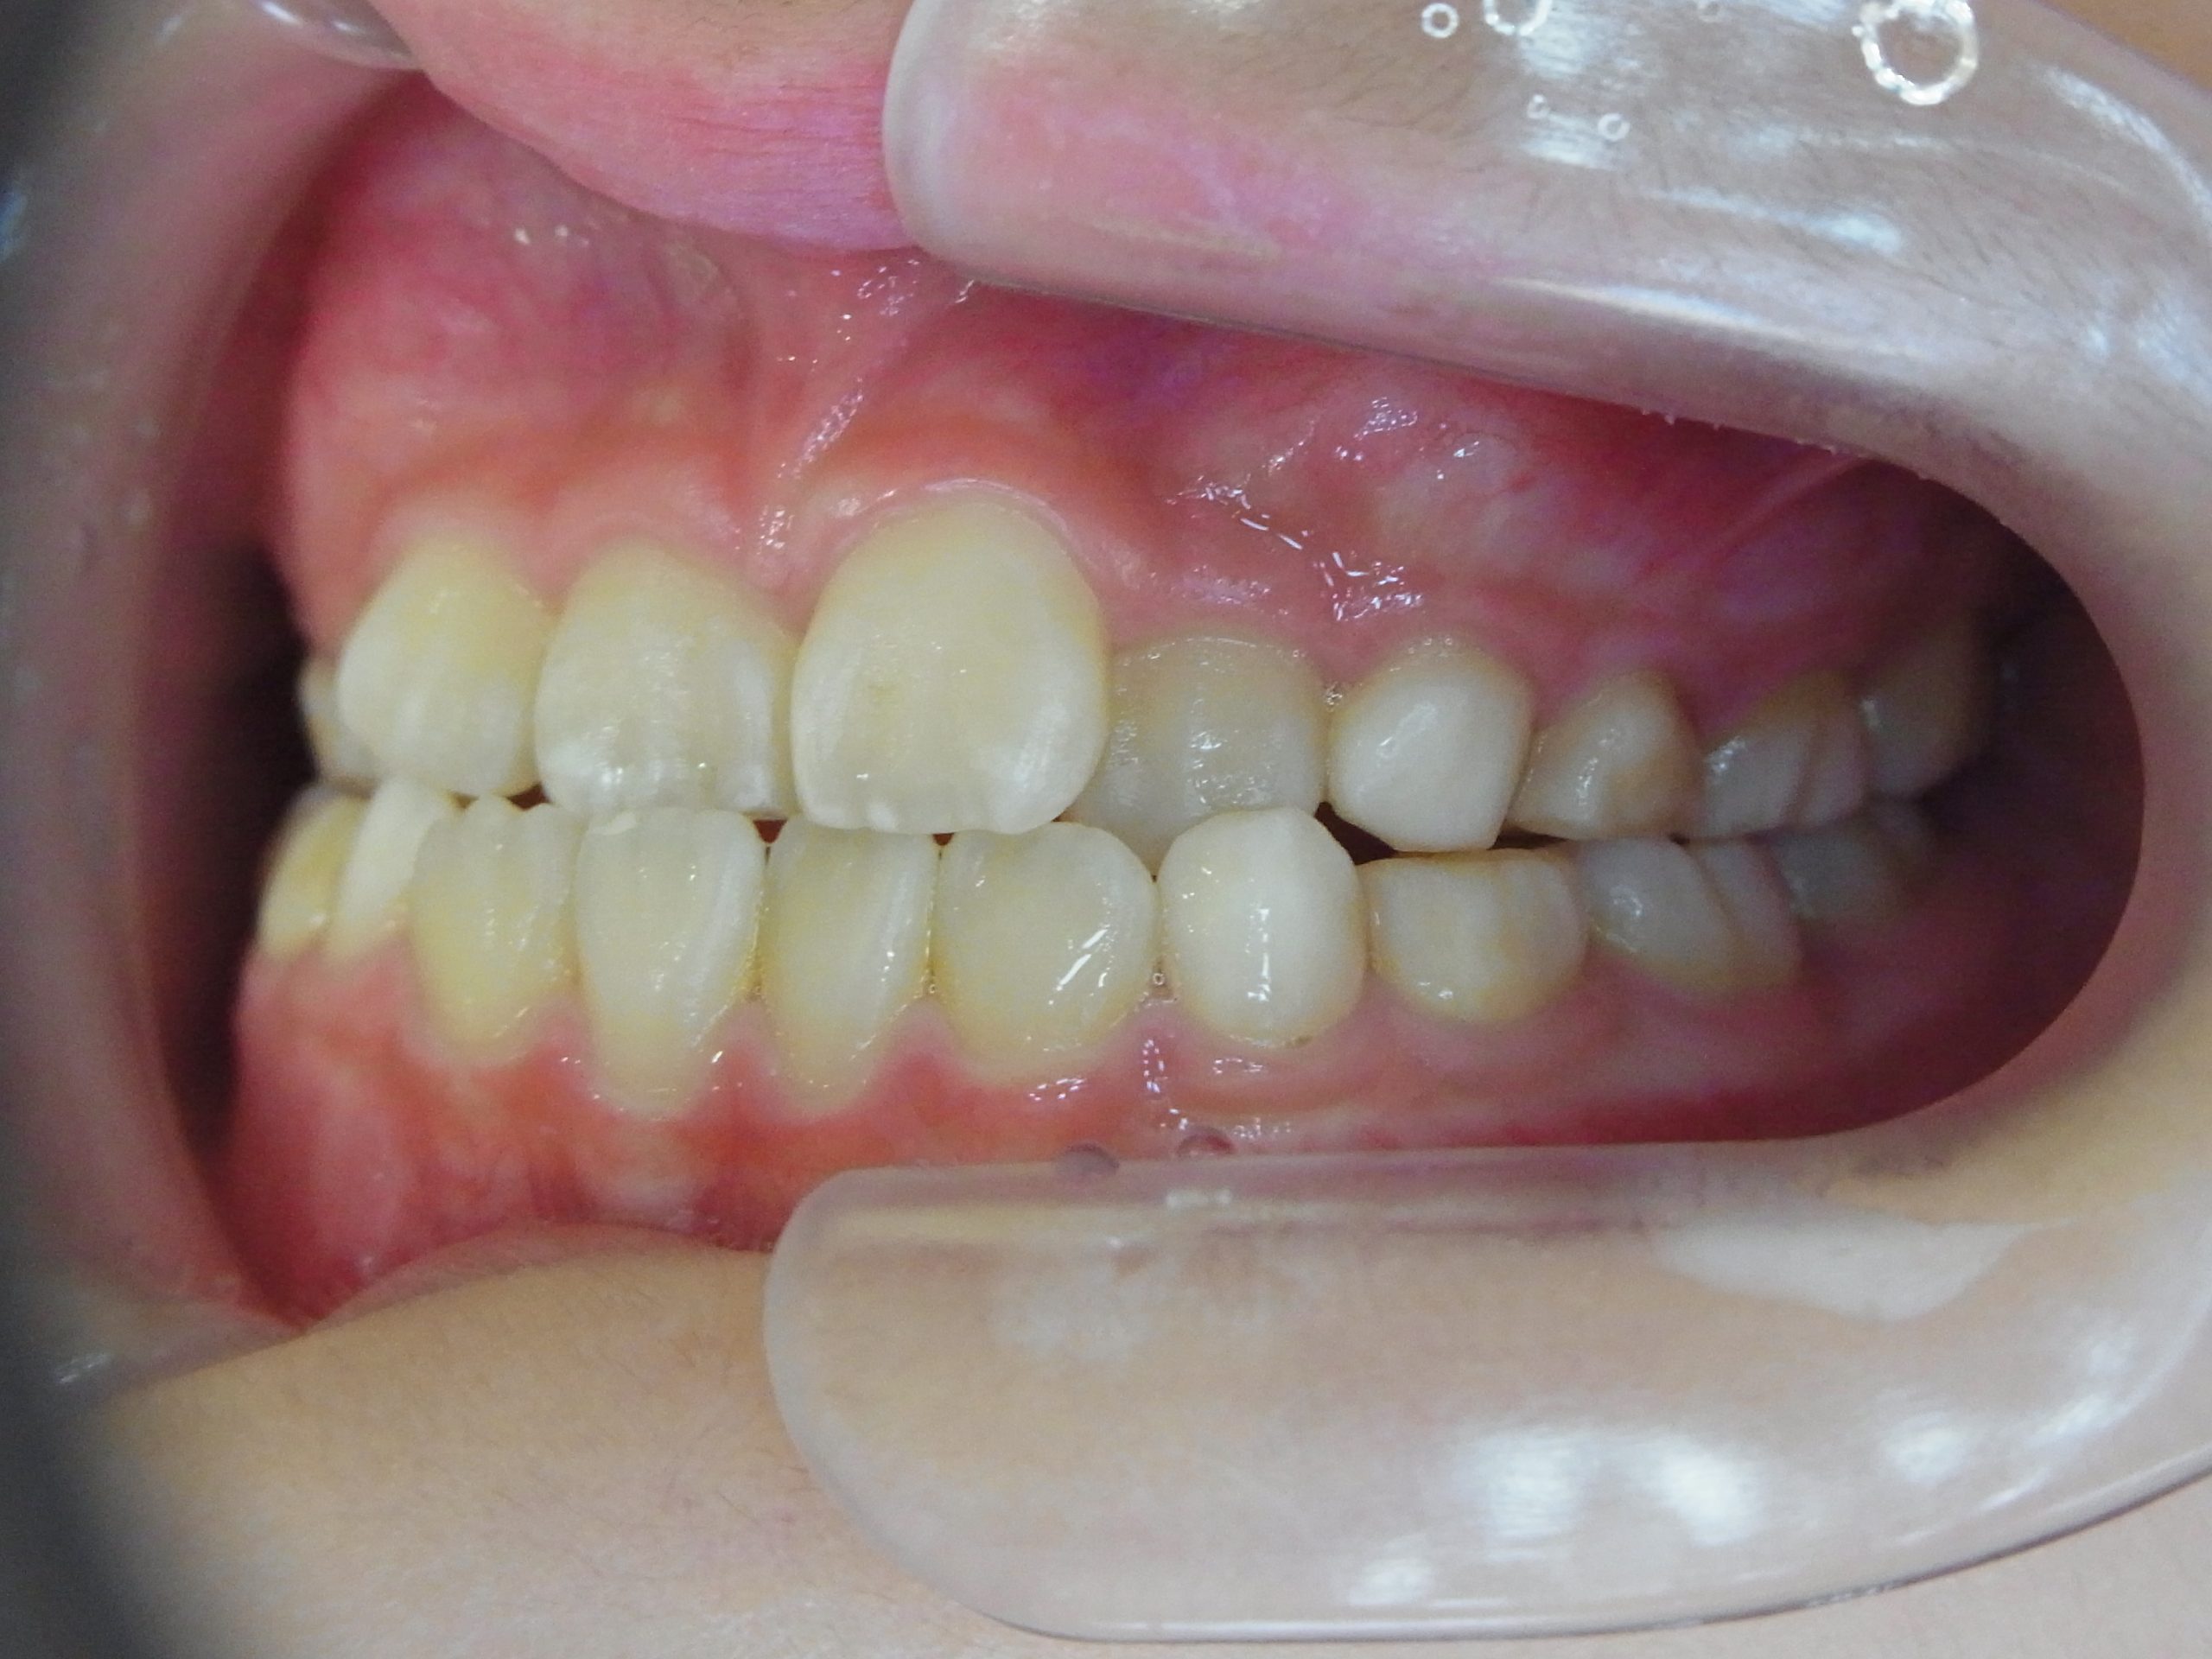

【小学生】マイオブレース矯正 受け口を改善 ③

小学生で開始

マイオブレース

受け口

非抜歯

1期治療のみで改善

Before

After

治療期間

2.3年

治療開始

10歳

種類

マイオブレース矯正

使用装置

機能矯正装置 上顎前方けん引装置

コメント

現在は治療終了後10年程経っています。

今では とても綺麗なお嬢さんになられています。